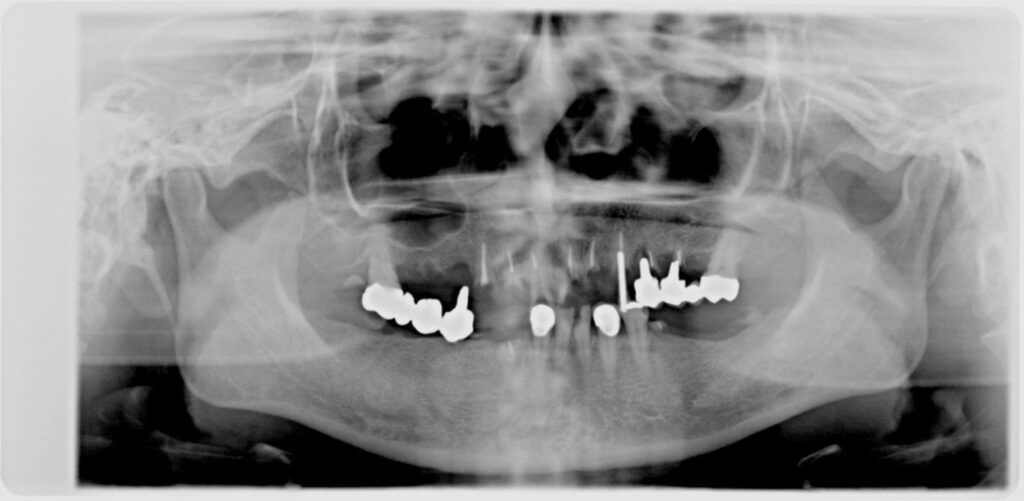

患者様のお悩み

食事ができない

治療法・使用素材

インプラントを用いた全顎的咬合治療

患者様の年代

40

治療開始年齢

49

治療にかかった期間

2年

性別

女性

治療前